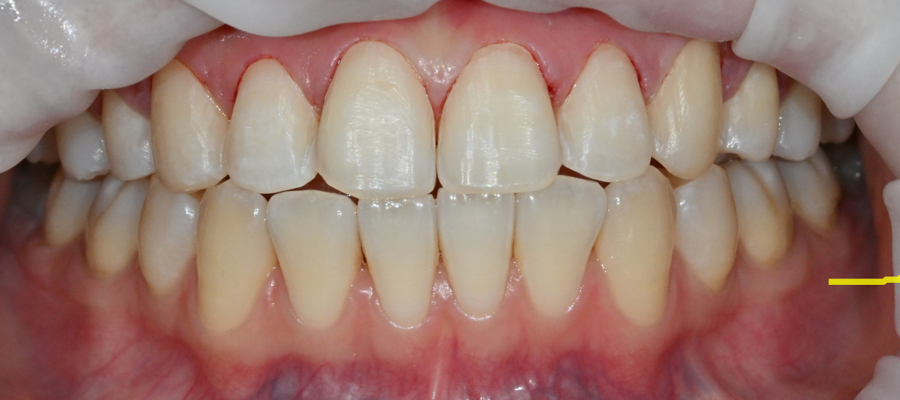

The main concern at the first visit

The patient was less concerned about dental health itself

and more worried that the front-tooth line visible when smiling

and the overall impression did not look well-balanced.

The front teeth were slightly uneven in length,

and the alignment was subtly off,

so the patient felt the teeth looked irregular

when taking photos or smiling.

Fortunately, there were no cavities or gum disease,

and after a comprehensive review of tooth thickness and alignment,

the teeth were determined to be suitable for veneers without tooth reduction.

Along with panoramic X-rays,

we took intraoral and extraoral photos, as well as front and side facial photos,

and analyzed the tooth length, degree of protrusion, and gum line together.